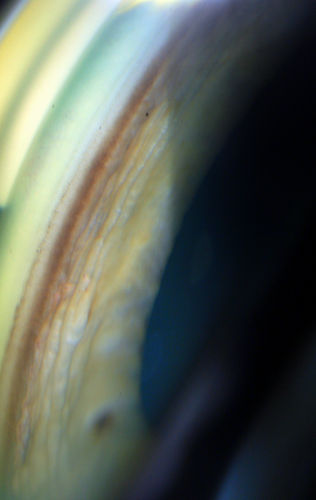

Gonioscopy, Pigment Dispersion Syndrome

Patient comes in with elevated pressures. Goinoscopy shows heavy pigment dusted off the iris into the trabecular meshwork. Laser procedure was done to break up the pigment for more aqueous flow.

Mayo Clinic Jacksonville, Florida

TOPCON D-90 SL/Nikon